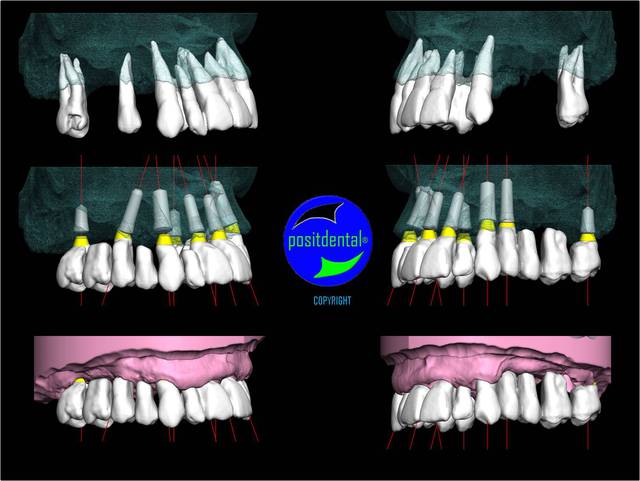

rendu 3D maxillaire sup, pano et photo

3D maxillaire inférieur et photo

Montage esthétique ou wax-up 3D